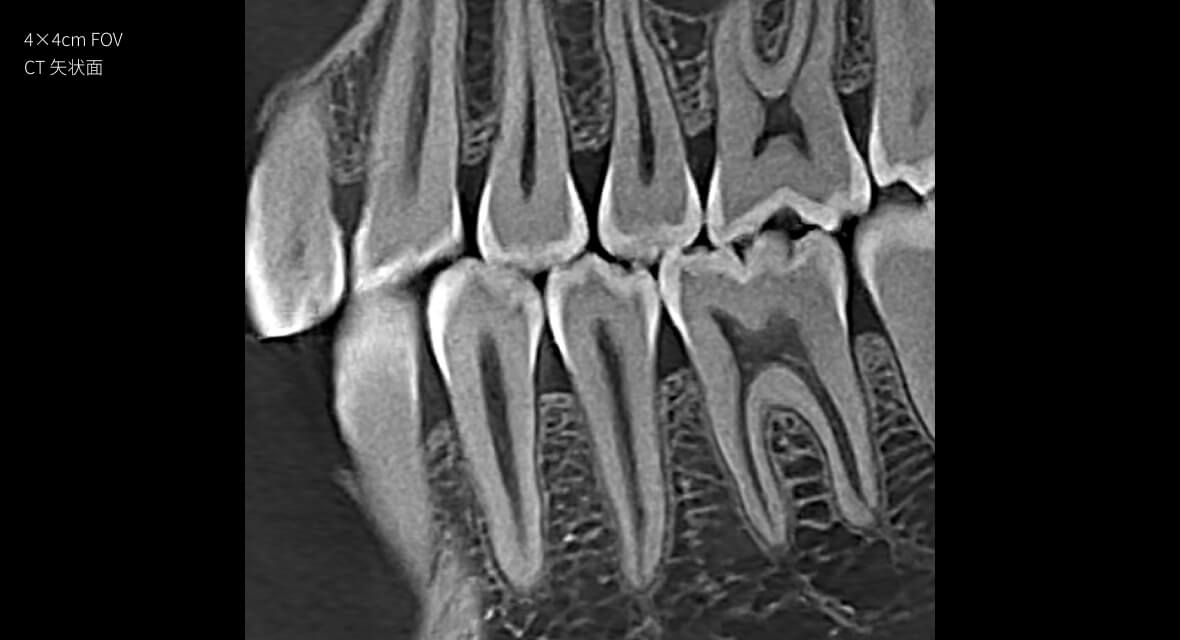

28lp/cm

高精準

Physics-driven系列偽影校正算法

實現高清精準成像

物理驅動

偽影校正算法